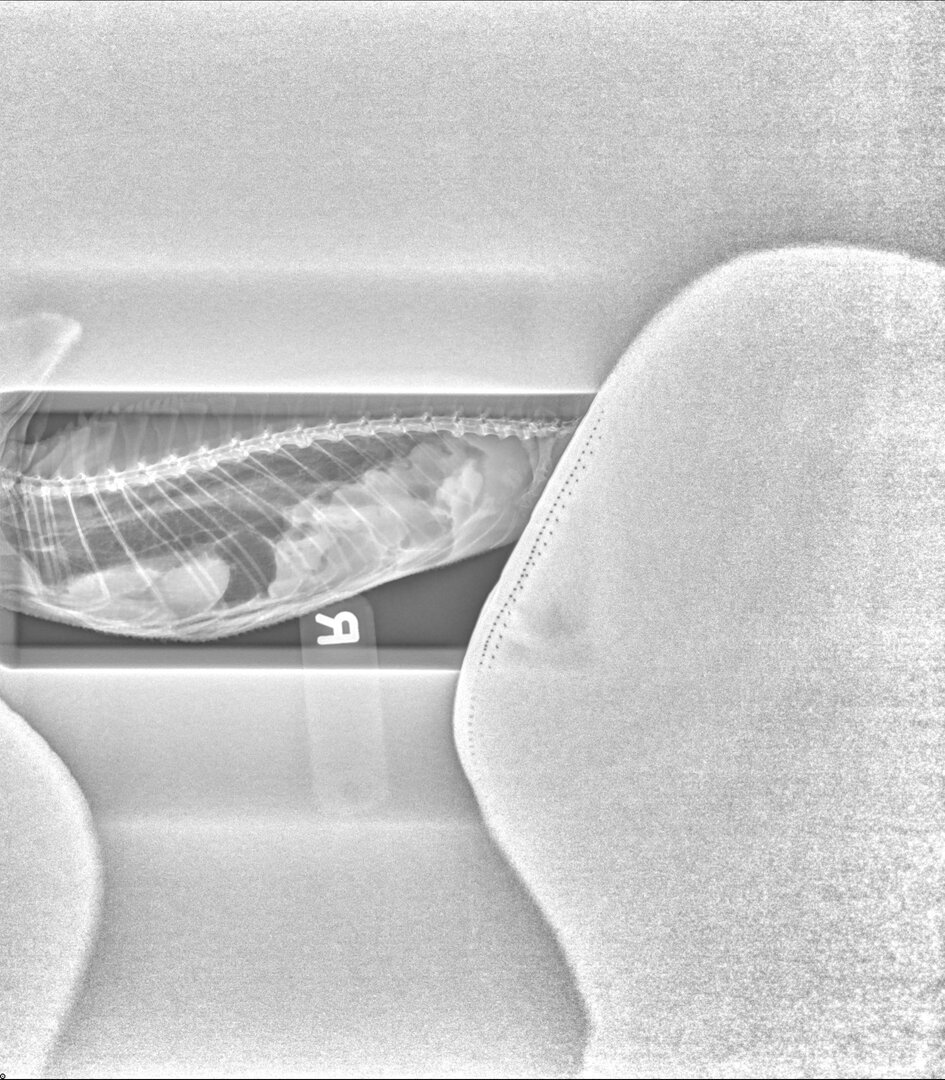

Here are Squirt's Xrays. I don't know how to look at those, but I'm worried about his tail. I think the rest of his parts look good.

• Newman,Squirt10.30.200002.jpg

Newman,Squirt10.30.200002.jpg

218.9 KB · Views: 156